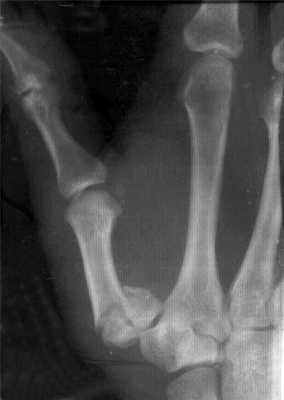

Рис. 36. Перелом крючковидной кости (указан стрелкой) при чрез- ладьевидно-чрескрючковидно-межпястно-латеролунарном вывихе кисти и энуклеации проксимального фрагмента ладьевидной кости с повреждением проксимальной запястной дуги у больного 37 лет в результате прямой травмы (рентгенограммы), а — в день травмы; б — через 10 нед после открытого вправления (предпринятого через месяц с момента травмы) с реплантацией фрагмента ладьевидной кости и костной пластики, с устранением расхождения поперечной запястной дуги и репозицией фрагмента крючковидной кости: отсутствие сращения крючковидной кости вследствие непроведения костной пластики и внутренней фиксации.

Н. Milch (1934) выделял две главные формы переломов тела кости: кнаружи от крючка (с лучевой стороны) и кнутри от крючка (с локтевой стороны). Переломы могут быть также косыми, поперечными, краевыми, локализоваться у основания или верхушки. В связи с преимущественно прямым механизмом травмы нередки расхождения фрагментов, повреждения близлежащих структур. Иногда переломы крючковидной кости сочетаются с повреждениями проксимальной запястной дуги, вывихами (рис. 36). При свежих повреждениях боли ощущаются в локтевой половине кисти проксимальнее основания IV—V пястных костей с локальной болезненностью и отеком. По рентгенограммам в прямой проекции, дополненной снимками в первой и второй косых проекциях, переломы тела обнаруживают без особых затруднений. Иногда иммобилизация при косых и продольных переломах не приводит к сращению даже в отсутствие заметных смещений, что зависит не от нарушений в